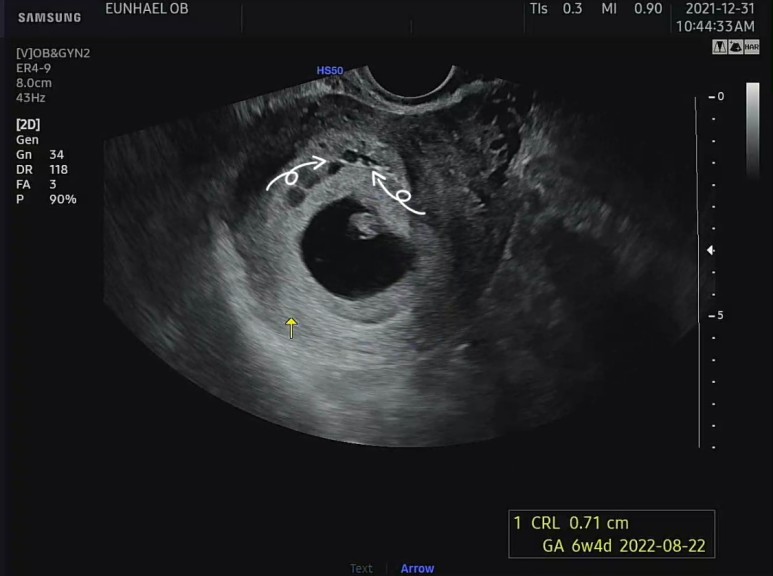

아침 일찍 병원에 가서 질 초음파를 하고, 우선 아기가 잘 있는지 확인했다

아가는 심장도 잘 뛰고 다행이 아주 건강했다. 이틀 전에 병원에서 도마뱀 모양의 초음파를 봤었는데, 이틀 전 모양과는 또 다른 모양의 아기가 초음파 속에 있었다. 아기집도 그새 좀 더 커져 있었다.

초음파 상에서 자궁벽 주변으로 피고임이 보였다.